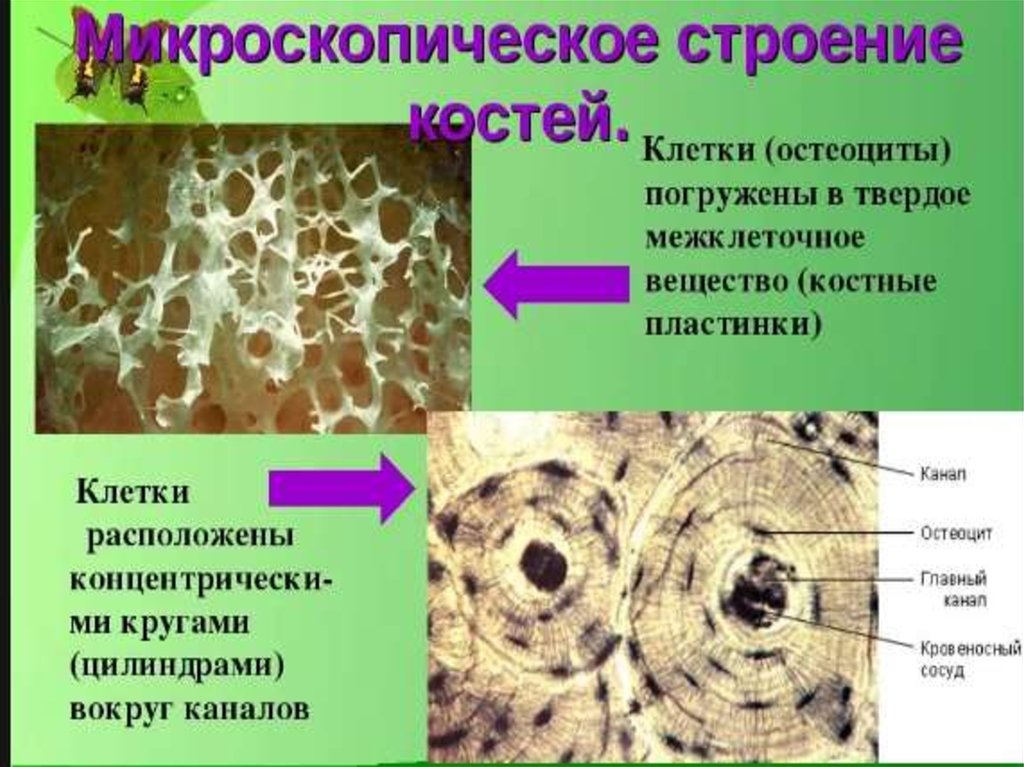

Структура грубоволокнистой костной ткани: наглядные примеры